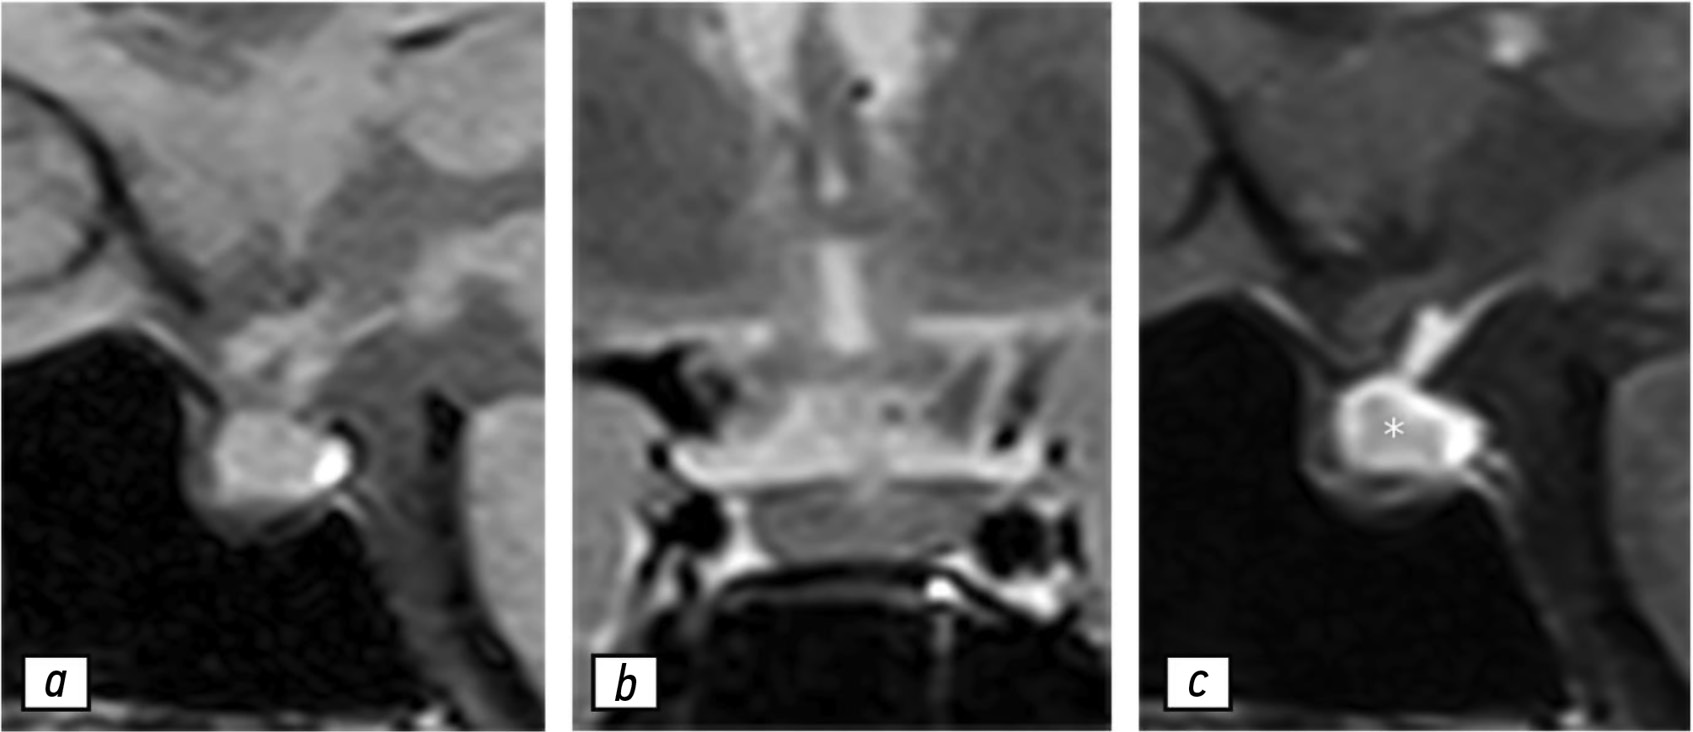

Hypophysitis is a rare inflammatory disorder that affects the pituitary gland and infundibulum, stems from autoimmune, infiltrative, infectious, or unknown causes. Its clinical diagnosis can be challenging because several pituitary lesions, including adenomas and metastases, may clinically present with similar characteristics. Magnetic resonance imaging is crucial for diagnosing suspected cases of hypophysitis and categorizing them as adenohypophysitis (anterior pituitary gland involvement) or infundibulo-neurohypophysitis (pituitary stalk and posterior pituitary involvement). Hypophysitis can be categorized as primary (autoimmune) or secondary due to local lesions (e.g., granulomas, cysts, adenomas) or systemic diseases (e.g., sarcoidosis, Wegener’s granulomatosis). Different factors may have impact on clinical course of hypophysitis. Among them background treatment. These cases have not been sufficiently studied and are practically not presented in publications.

A 37-year-old female with a history of hyperprolactinemia was being treated symptomatically with cabergoline. At first magnetic resonance imaging heterogeneity of the hypophysis was revealed. In September 2021 the follow-up magnetic resonance imaging revealed an increase in the size and heterogeneity of the pituitary gland. In December 2021, the patient developed severe COVID-19-associated pneumonia and was treated with corticosteroids and oxygen support. In May 2022 magnetic resonance imaging revealed a marked increase in the size and heterogeneity of the pituitary gland. Significant clinical and radiological improvement were stated after adding prednisone (10 mg in the morning and 5 mg in the evening) to her treatment.

The patient was followed-up during the COVID-19 pandemic. The management and imaging studies of such patients may be tricky due to the effects related to COVID-19 and its treatment.

During monitoring of hypophysitis, physicians should consider the impact of COVID-19 treatment, particularly corticosteroid therapy, when evaluating the radiological changes.